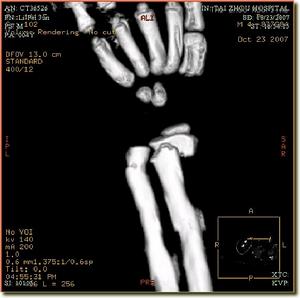

3、X線檢查

除正、側位X線攝片外,尚應根據傷情拍攝特殊體位相,如開口位(上頸椎損傷)、動力性側位(頸椎)、軸位(舟狀骨、跟骨等)和切線位(髕骨)等。複雜的骨盆骨折或疑有椎管內骨折者,尚應酌情行體層片或CT檢查。

無移位者用上肢石膏或石膏托功能位固定,有移位者經復位後達到或近於解剖復位者,

![]() | ![]() |